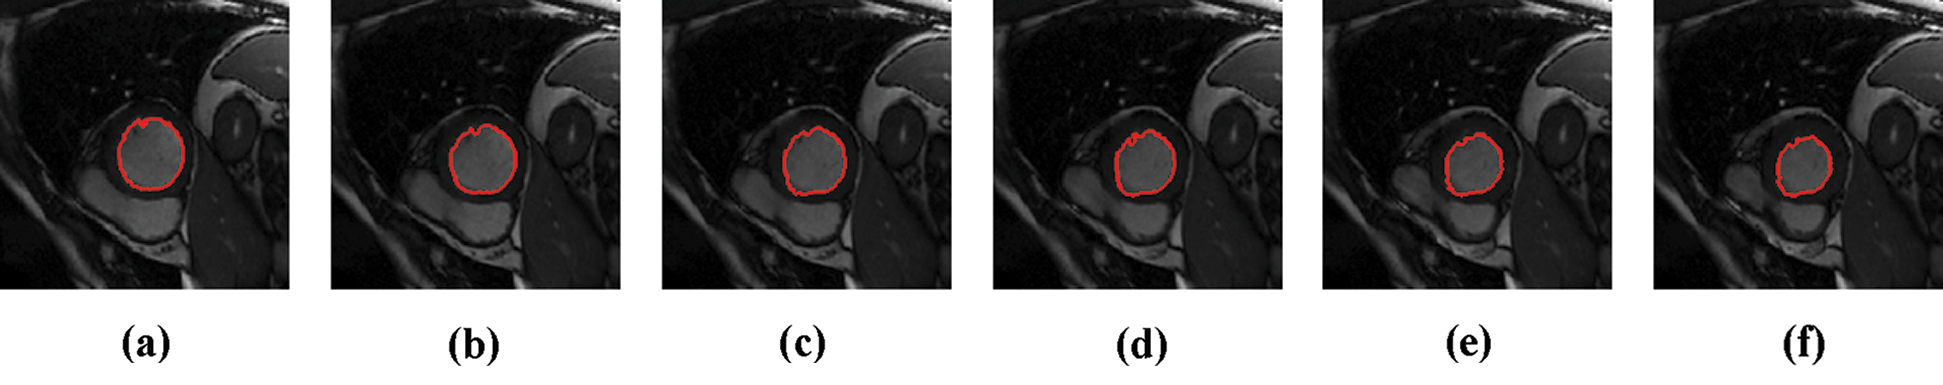

The experimental results are categorized into two distinct sections to underline both the segmentation and psoriasis lesion localization results. The presented results of this paper were obtained through using different 6 techniques to 300 sets of CVD. In this paper, multi-axis CMR database was used in three axes for 6 case studies to provide the results of various segmentation schemes. In this section, the employed techniques for studying and segmenting medical images are executed using MATLAB. Figs. 1a–1f present the Caselles segmentation technique results. These results indicate that this technique gives better results when the initialization step is suitable and the image has a high intensity gradient at the edge between the cavity and the myocardium of LV. It is also clear from the results that the blood pool segmentation depends on the boundary features. Both of Li and Bernard segmentation techniques show a wide band segmented results that are not reasonable to the blood pool segmentation as shown in Figs. 2 and 3. This is apparently visible in the Bernard segmentation technique where the segmentation partitions of each slice to bright regions and dark regions cannot separate the LV cavity from other parts of the image. The relationship between each pixel and its adjacent neighbors is considered. As it could be seen from Figs. 4a–4f, the blood pool of LV is purely delineated. That is the resulted segmented image of the Chan-Vese technique appears well-defined. Based on the obtained results, one can say Chan-Vese technique works well with homogenous regions such as cardiac images. In addition, the resulted segmented slices appear of high smoothing degree as well. The segmented images from the blood pool of LV obtained using the Lankton-Yezzi segmentation is presented in Figs. 5a–5f. As it could be seen from these figures, the quality of the segmentation process using the Lankton-Yezzi technique depends on the initialization. As it could be seen from Figs. 6a–6f, the two cycles of Shi-Karl segmentation technique produce good quality segmentation to the LV blood pool.

Figure 1: Sample results of Caselles technique